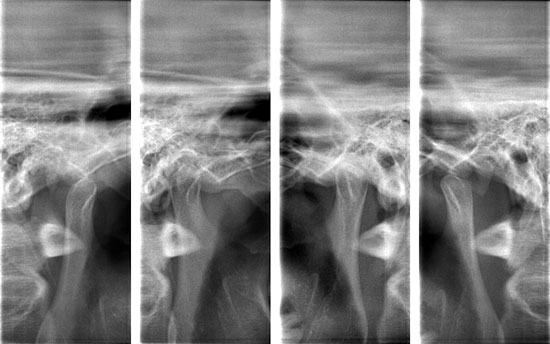

下記レントゲン画像のように横向きに生えていると、7番目の歯と親知らずの隙間に細菌が溜まり、虫歯になったり、周囲の歯肉が腫れたりする原因となります。

親知らずの症例